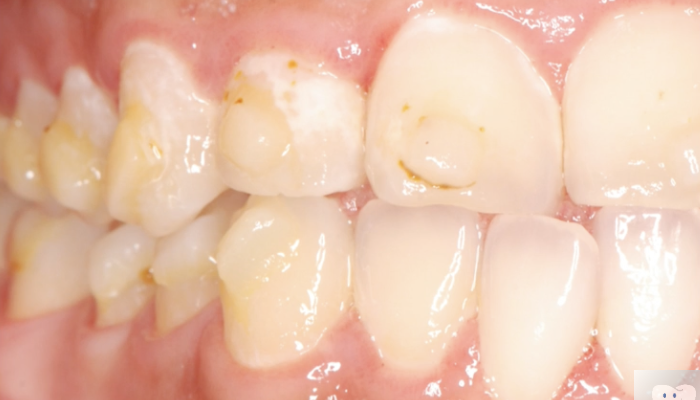

ワイヤー矯正後

マウスピース矯正後